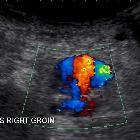

Ultrasound

Ultrasound is the quickest and best modality for assessment. Due to the turbulent forward and backwards flow, a characteristic yin-yang sign may be seen on color flow while a "to-and-fro" pattern may be seen with pulsed Doppler. Ultrasound can also be used for therapeutic probe compression (ultrasound-guided compression), providing real-time feedback of the thrombosing pseudoaneurysm.